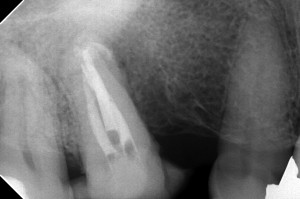

術前です。

近心の6があったであろう辺りにサイナストラクトがあり、ブリッジを外して根管治療をした症例なんですが、根管長を測り、根管充填をしようとシーラーを入れて遠心頬側根を重点したら、近心の根尖付近にシーラーが見えまして・・・

根充後のデンタルです。

MBとBDが完全に合流してたんですね・・・

サイナストラクトの痕に沿ってシーラー流れておりやす・・・まあ、問題ないと思います。

根尖性歯周炎は、長期化すると、根尖孔外から、徐々に吸収されていくので、根尖は広くなっていきます。(前医が大きく広げていることもありますが)

そうすると、このようにシーラーパフと呼ばれる現象が起こります。